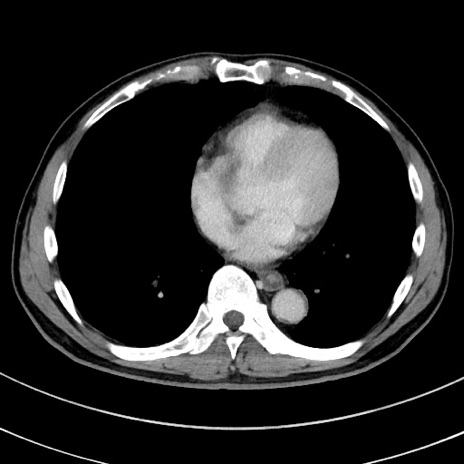

冠状断像

【症例】 60歳代男性

【主訴】 黒色吐物

【現病歴】 4日前から嘔気自覚、2日前の朝食後にも嘔気あり、自分で手で嘔吐反射起こし嘔吐したところ血が混ざっていたため受診。

【既往歴】 5年前汎発性腹膜炎を伴う急性虫垂炎で手術、高血圧、前立腺肥大症、高脂血症

【身体所見】 腹部正中に手術癩痕あり 腹部平坦・軟圧痛なし膨満感あり

【データ】WBC 8400、CRP 4.54